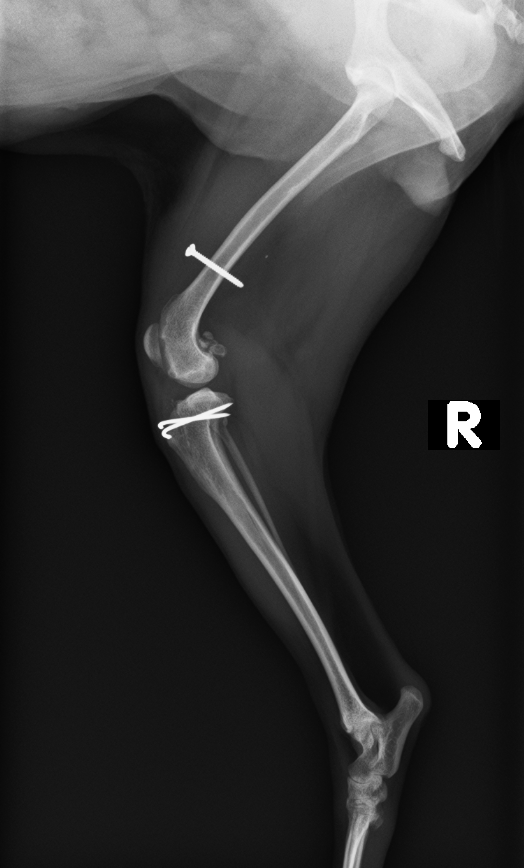

レントゲン、CT検査より右膝蓋骨外方脱臼

筋膜リリース、外側広筋リリース、造溝術、脛骨粗面転移、関節包・筋膜縫縮、外側関節方解放